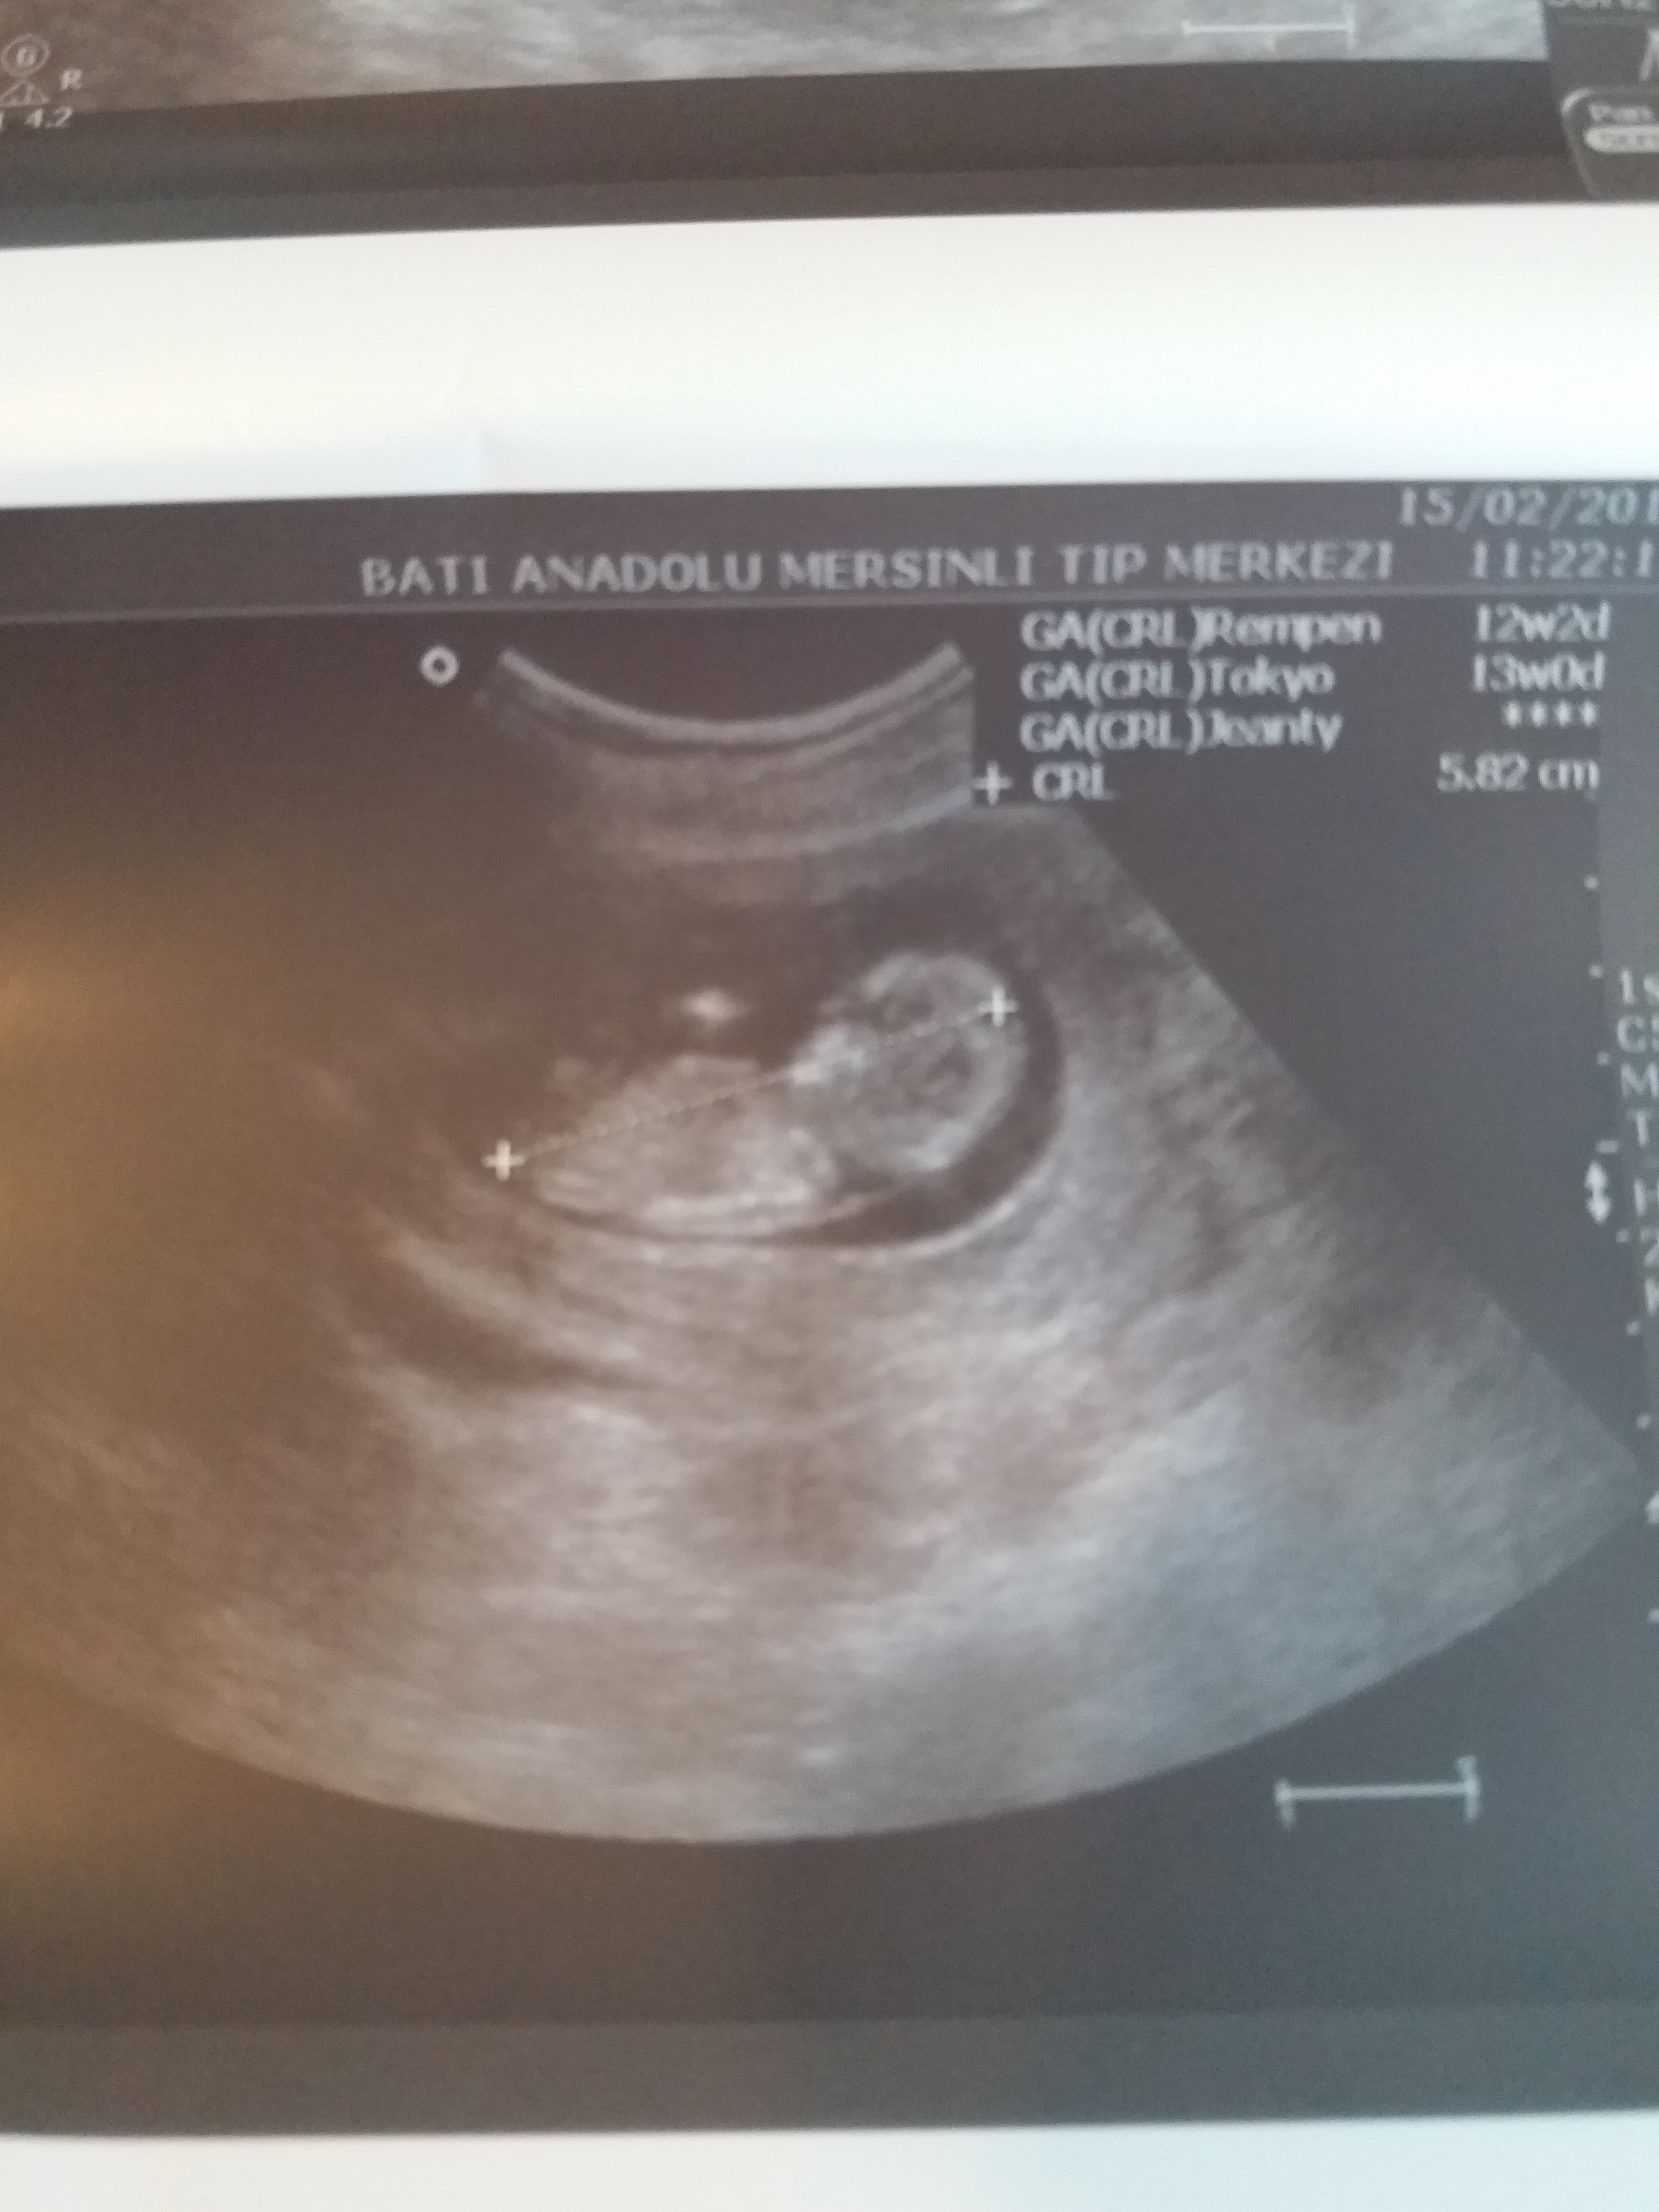

Daha önce de belirtildiği gibi, hem erkek hem de kız fetusların gelişme aşamalarında genital bir tüberkül vardır. Bu genital tüberkül bir nub olarak adlandırılır.Nub Teorisini kullanarak bebeğinizin cinsiyetini belirlemek, büyük oranda ultrason resmine bağlıdır. Bu, nub resminin sonucu belirlemeniz için mükemmel olması gerektiği anlamına gelir.

Resimde gördüğünüz gibi üst taraftaki çıkıntı paralel ise bebek kız, 30° lik açıyla yukarı bakıyorsa bebek erkektir.

Gebeliğin 9. haftası fetusun bacaklarının arasın da küçük bir çıkıntı görülür. Gebeliğin 12. ve 14 haftası bu topak çıkıntı nın açısı değerlendirilerek , cinsiyet tahmini yapılır. Çıkıntı kızlar da 30 derecenin altın da ve düzdür erkekler de ise 30 derecelik açıdan büyüktür.

Görünürlük , omurga ile ilgili genital tüberkül açısı , Gölgeler ve erkek belirteçler ve topak çevreleyen ucu , Gebelik yaşına göre uzunluğu da dahil olmak üzere, şekil.. Nub teorisi ile cinsiyet belirleme de tarama omurga görüntüleme ve buna özü ilişkisini sağlamak için, profil görünümünde olmalıdır.